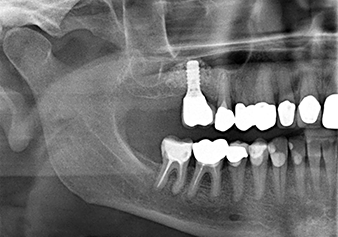

A 49-year-old female patient, a non-smoker and with nothing remarkable in her general medical history, was referred to our oral surgery practice for surgical extraction of tooth 16 and subsequent implantation. After the extraction, the patient experienced mild sinusitis trouble with the resultthat we initially waited six months before carrying out the measure. The residual bone height at the planned implant position measured 3-4 mm (Fig. 1 and 2).

Fig.1: Preoperative findings: The alveolar ridge has healed well, including sufficiently broad, keratinised gingiva.

The x-ray check shows a largely homogeneous peri-implant hard tissue structure

Fig.10: A good six months later, after the definitive crown had been incorporated, the x-ray check shows a largely homogeneous peri-implant hard tissue structure.